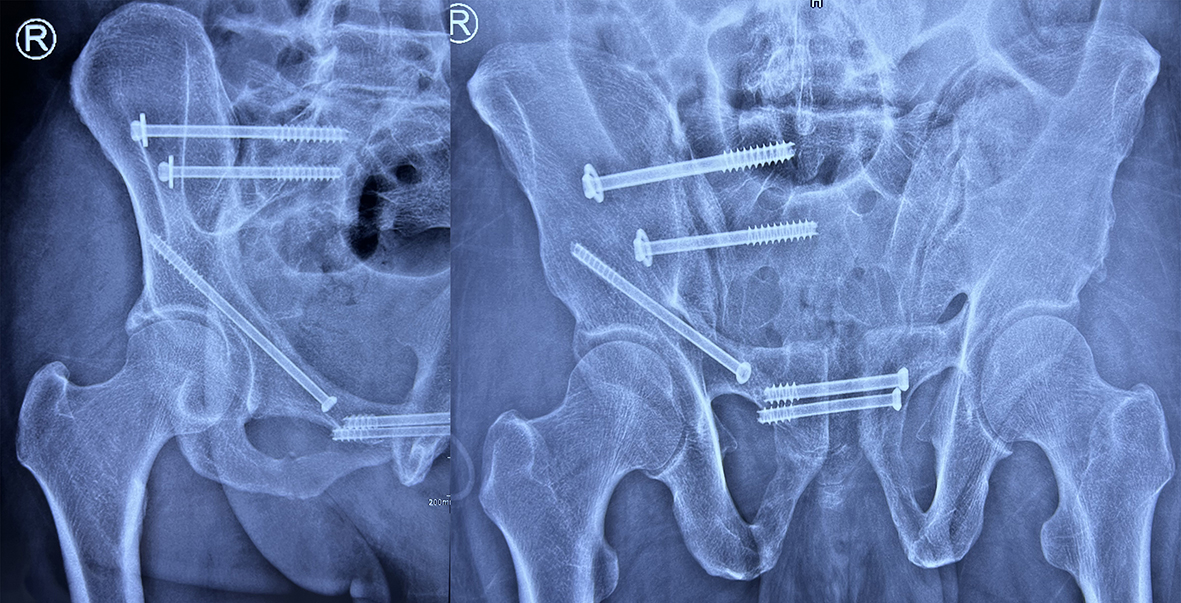

患者为59岁男性,重度肥胖,高血压,低氧血症。经外院保守治疗失败后转入兰大二院创伤骨科,入院后科室积极组织病情讨论,精心制定术前计划。在骨科主任医师汪玉良、刘京升、周斌的指导下,骨科副主任医师雷栓虎徒手植钉,完成骶髂螺钉、逆行前柱螺钉、耻骨联合螺钉多向骨盆通道螺钉固定,手术切口仅4个不足1cm的伤口,术中出血约10ml。手术以微创的方式解决了复杂的骨盆骨折,术后患者疼痛明显缓解,术后2天即可下地行走,极大的缩短了卧床时间,加速了患者早期康复。

骨盆骨折约占全身骨折的3%,其中10%为不稳定骨折,死亡率高达8%-37%,骨折类型多种多样,常伴随大量失血以及其他脏器损伤,手术治疗难度大、风险高。以往手术需切开复位钢板内固定治疗,手术创伤大、出血多、并发症高,而骨盆通道螺钉技术是国际上先进的骨盆骨折微创治疗手段,在骨盆有限三维空间内设计出骨性安全固定通道,手术切口小、出血少、并发症低,术后患者恢复快。但由于骨盆解剖复杂,手术操作难度大,因此该项微创技术在国内没有普及。近年来,兰大二院创伤骨科积极推进学科亚专业化,致力于四肢、骨盆、多发骨折的诊治处理,并承担甘肃省急救中心急诊骨折患者的抢救与诊治,科室长期与北京积水潭、上海六院等国内知名院校合作交流,率先在甘肃省开展多项新技术,培养了一支高素质的专业队伍,使每位患者得到及时、规范的治疗。